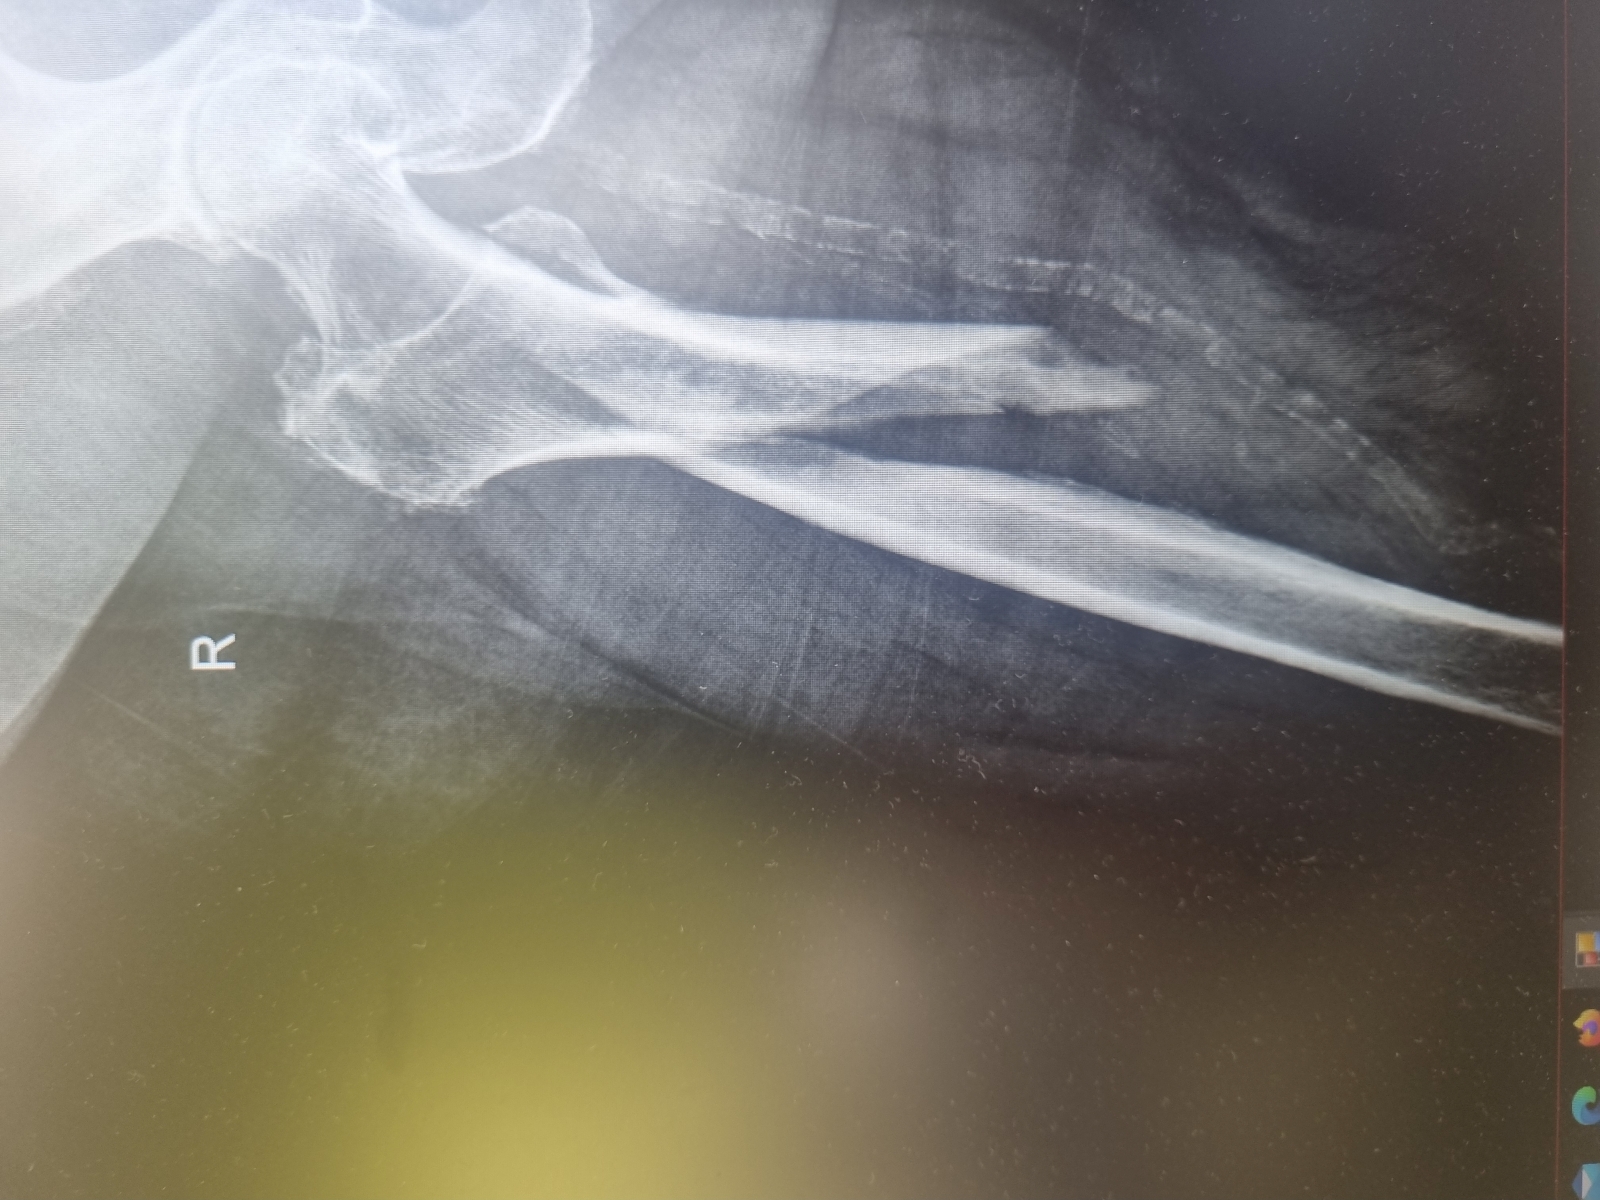

Moja praca w RTG

Miednica i kończyna dolna